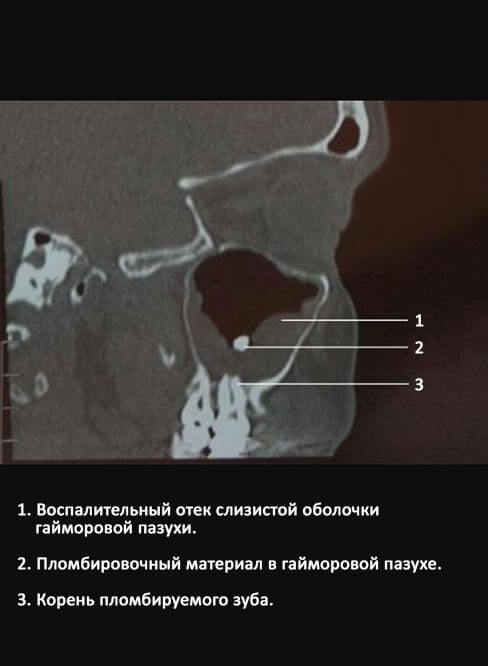

Если у человека сильный иммунитет, то возможно развитие заболевания при попадании цинка в гайморову пазуху в результате пломбирования зубов верхней челюсти. Цинк положительно влияет на размножение грибков и прорастание их спор.

Сначала происходит активное увеличение мицелл. Они образуют особый шар, который быстро увеличивается в размере и заполняет область околоносовой верхнечелюстной пазухи, часто не вызывая большого дискомфорта у человека.

Возможно обнаружение грибов даже у абсолютно здоровых мужчин и женщин, не входящих в группы риска. Иногда заражение происходит случайно, например, после пломбирования зубов верхней челюсти.

Согласно исследованиям, проведенным учеными, подтверждается, что цинк играет роль катализатора в развитии грибковых инфекций. Он усиливает тяжесть состояния у пациентов с аспергиллезом.

Поэтому необходимо обратить внимание на выбор материалов, которые использует стоматолог. Если есть такая возможность, рекомендуется просить использовать материалы, не содержащие цинковые соли.